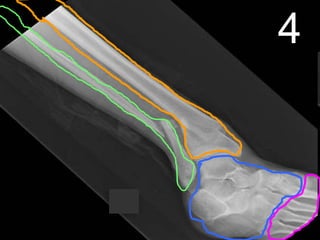

Long Bone

Copyright © 2010 Ryan P. Murphy

Cartilage

Ligament

Compact

Soft / Spongy

Yellow

Marrow

Fats

Red

Blood